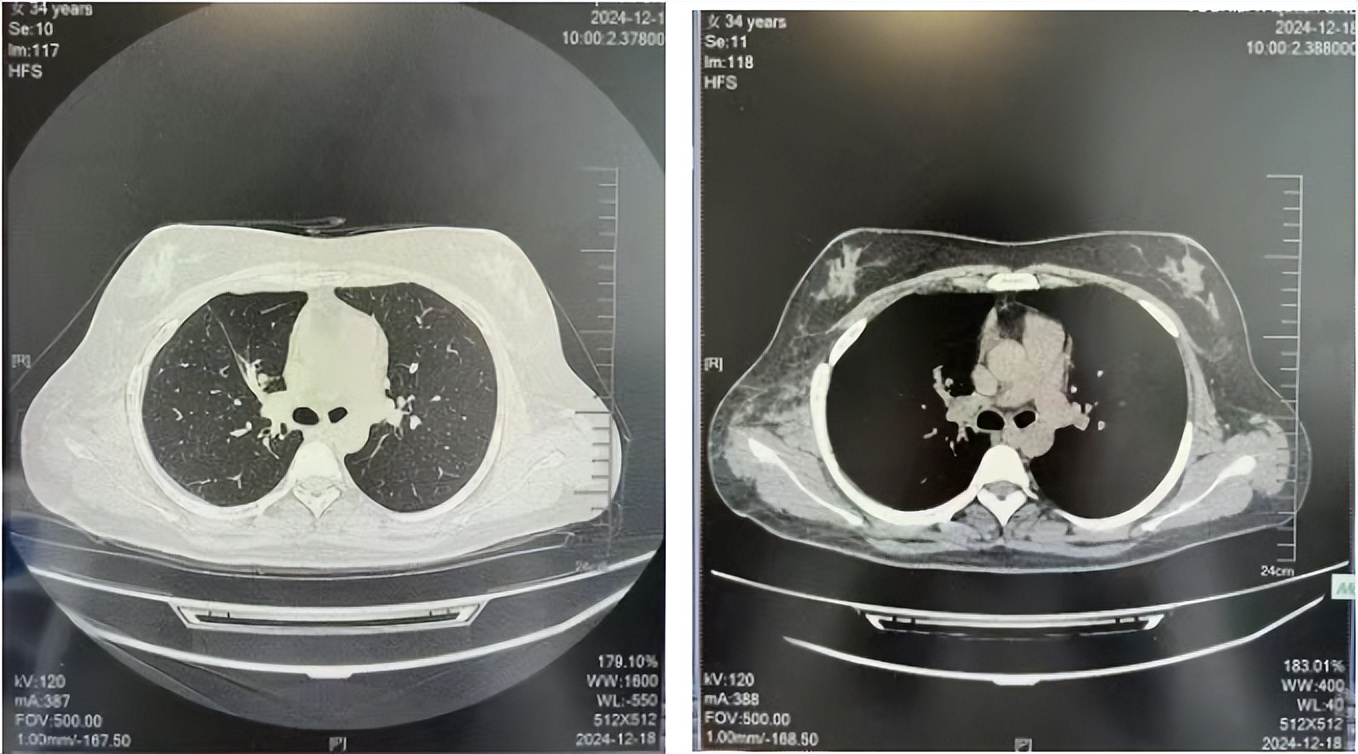

2016年1月复查CT提示支气管截断可见新发小结节,一线治疗采用培美曲塞+DDP方案化疗4周期(培美曲塞3.36,DDP 480mg)。化疗后复查胸部CT:右肺见不规则结节样影,最大层面大小约19mm*8mm,较前比较明显增大,疗效评估PD。2017.3-2017.4予单药多西他赛化疗3周期,疗效评估SD。2018年5月末复查CT提示结节较前增大,评效为PD,2018年6-10月予多西他赛+CBP化疗4周期,疗效评估SD。2022年5月患者出现活动后气短,复查胸部CT示右肺膨胀不良;右侧胸腔积液增多。胸腔积液包埋病理示符合肺腺癌细胞。行NGS基因检测:EML4:exon13-ALK:exon20融合。PD-L1(克隆号22C3)TPS<1%。

2024.12